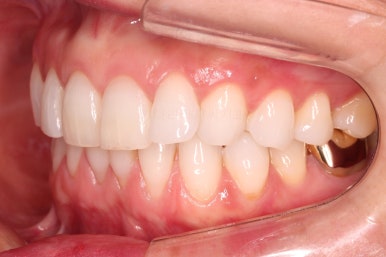

초진 시 입안의 모습입니다.

환자분이 원하셨던 부분은 윗니 작은 앞니가 하나 튀어나와서 개선하고 싶어하셨습니다.

부가적으로 아랫니 앞니가 마모가 심하여 높낮이가 달라보이는 점이었는데요.